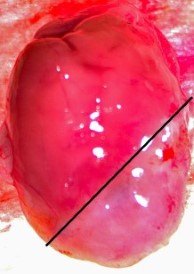

Chronic Ischemia (MI)

4-7 Days Post MI Average 30% Infarct Area. Model Developing Athero